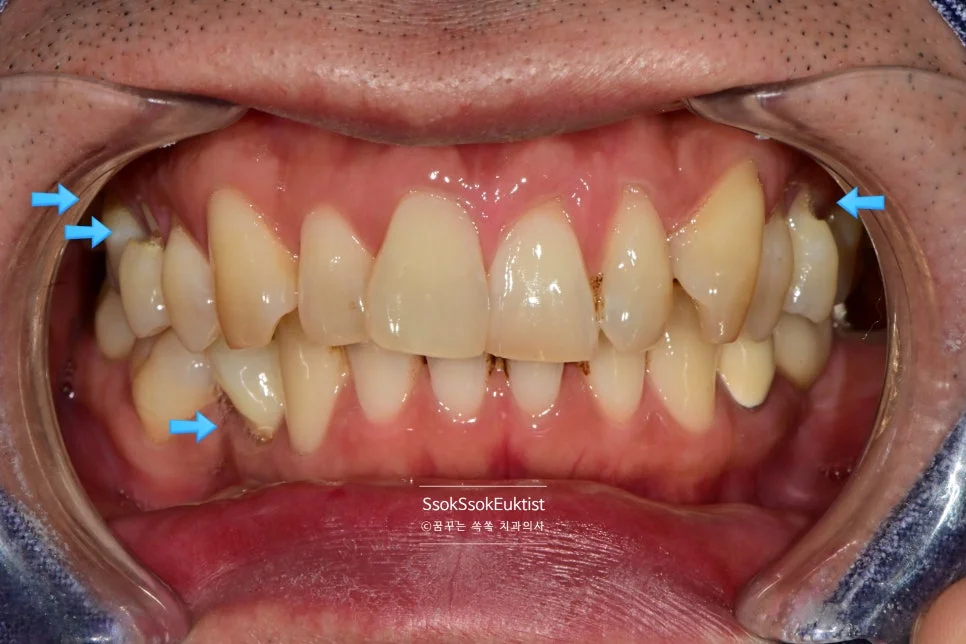

화살표로 표기된 치료 계획 — 앞쪽은 레진, 어금니는 GI

화살표로 표기된 것과 같이 눈에 보이는 앞 쪽 치아는 레진으로, 큰 어금니는 GI로 계획을 세웠는데요.

결과는 과연 어떻게 되었을까요?